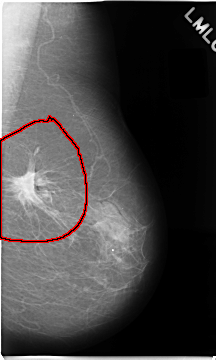

C_0079_1.LEFT_MLO

FILE: C_0079_1.LEFT_MLO.OVERLAY

TOTAL_ABNORMALITIES 1

ABNORMALITY 1

LESION_TYPE MASS SHAPE IRREGULAR MARGINS SPICULATED

ASSESSMENT 5

SUBTLETY 5

PATHOLOGY MALIGNANT

TOTAL_OUTLINES 1

BOUNDARY